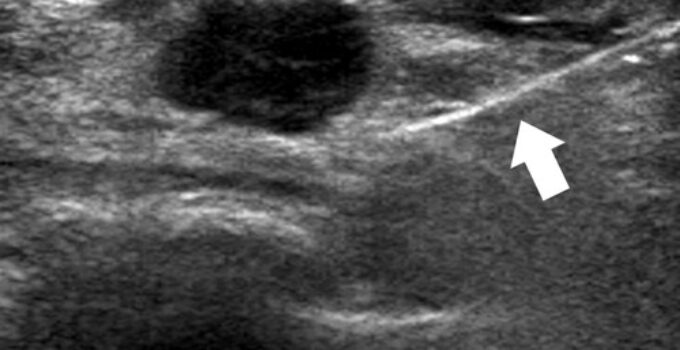

خزعة موجهة بالموجات فوق الصوتية. تستخدم هذه الطريقة صور الموجات فوق الصوتية لكتلة الثدي. تساعد هذه الصور في توجيه الإبرة إلى موقع الخزعة الدقيق.

يمسك اختصاصي الأشعة جهاز الموجات فوق الصوتية بالثدي ، ويحدد الكتلة ، ويحدث شقًا صغيرًا لإدخال الإبرة ، ويأخذ بضع عينات من الأنسجة.